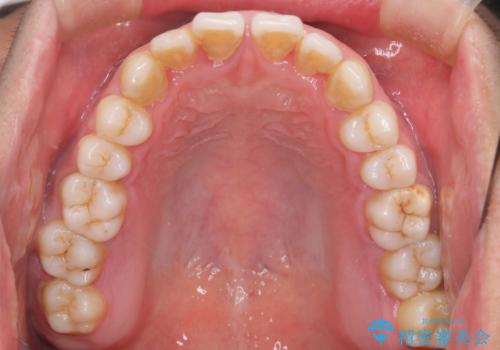

- 前歯のすきっ歯が気になると来院された患者様です。

前歯の隙間をマウスピース矯正(インビザライン)を使用して、閉じていきました。